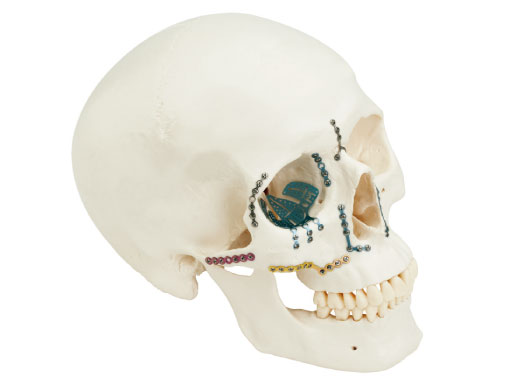

Matrix Midface System

The new matrix midface plate and screw system is intended for use in selective trauma of the midface and craniofacial skeleton; craniofacial surgery; reconstructive procedures; and selective orthognatic surgery of the maxilla and chin. One of the main intentions was to make the system flexible and easy to use.

The system offers a full range plate selection for NOE, ZMC, LeFort I, and a variety of other craniofacial indications made out of commercially pure titanium. Four thicknesses are available: 0.4mm (silver), 0.5mm (blue), 0.7 mm (pink), and 0.8mm (gold). The color coding designates the plate strength.

In April 2021, the new 1.3 and 1.5 mm plates and screws are aligned with the Matrix concept providing low profile plates and screws in a modular system with a wide range of plate shapes and screw options for fracture fixation. The new 1.3 mm screws (existing Matrix Screws are 1.55 mm in thread diameter) have allowed the distance between the screw holes in the plates 1.3 to be significantly reduced, providing more fixation options in the smaller plates (Fig 1). The 1.3 mm screws are not compatible with the existing Matrix plates 1.5 designed for 1.55 m screws and vice versa. The instrumentation for both Matrix Systems is identical. A smaller 1.0 mm drill bit, required for the 1.3 mm screws, has been included from the COMPACT Midface System. With the inclusion of new plates and screws, the MatrixMIDFACE System supersedes the COMPACT Midface System and offers implants in a range of sizes and shapes suitable for a variety of applications.